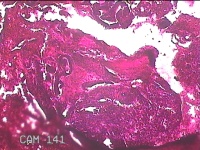

左宫角组织

性别

女

年龄

35岁

临床诊断

子宫角组织占位待查 人流术后 疤痕子宫

一般病史

人流术后20天,发现宫腔占位数天。

标本名称

大体所见

纱布一块,内有灰白暗红色不规则碎组织0.8x0.5x0.3m一堆。